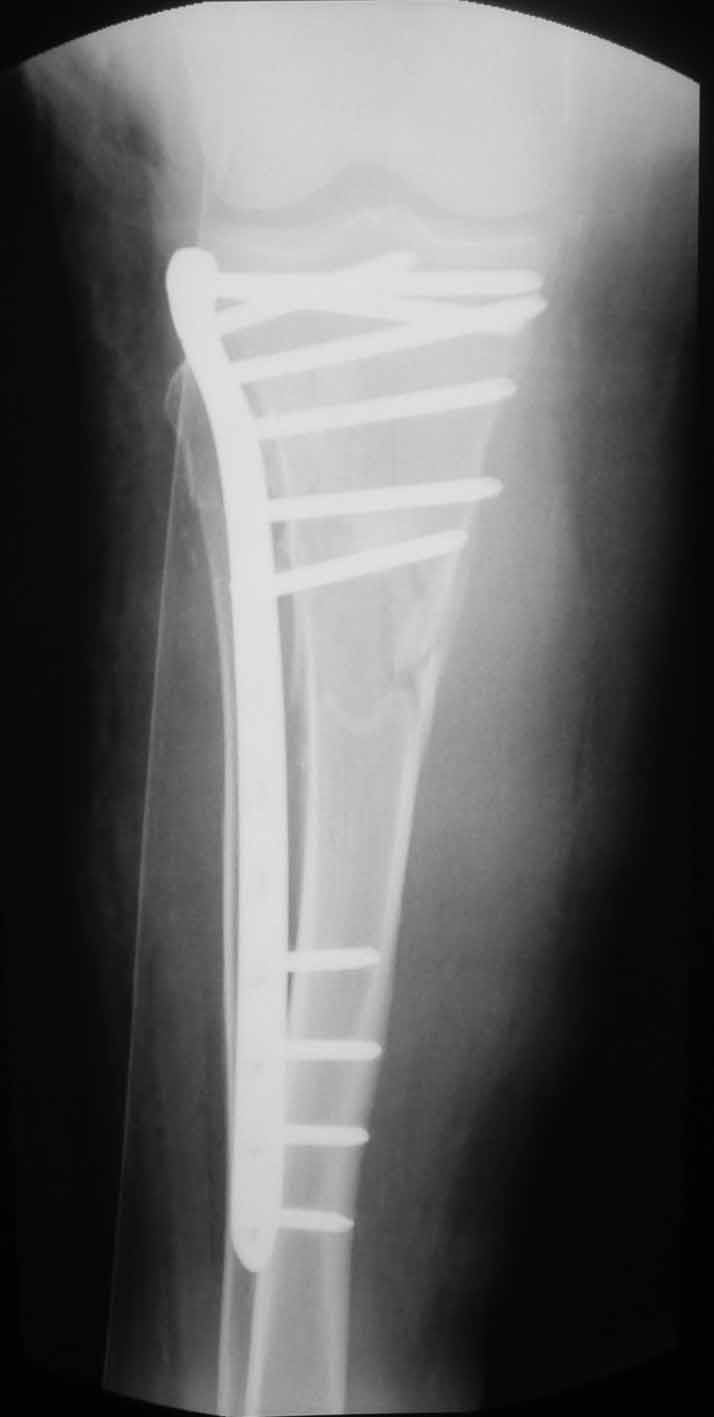

Пациентка 53 лет. ДТП 09.01.12: сочетанная травма: перелом 2-5 ребер справа, ушиб легких;

перелом обеих лонных костей без смещения; закрытый перелом проксимального конца правой

бедренной кости; открытый оскольчатый внутрисуставной перелом проксимальных концов

костей правой голени.

В нашей клинике 11.01 выполнен минимально инвазивный остеосинтез большеберцовой кости (снимки до операции не перефотографировал) с пластикой перемещенными лоскутами дефекта, образовавшегося вследствие некроза кожи на передней поверхности голени.